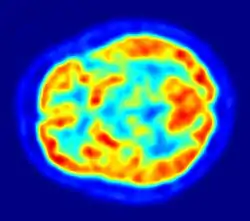

- 1983

- Positron emission tomography (PET, invented 1981) was compared to electroencephalography (EEG) and CT. It was found to be capable of locating epileptogenic cortical tubers that would otherwise have been missed.[50]